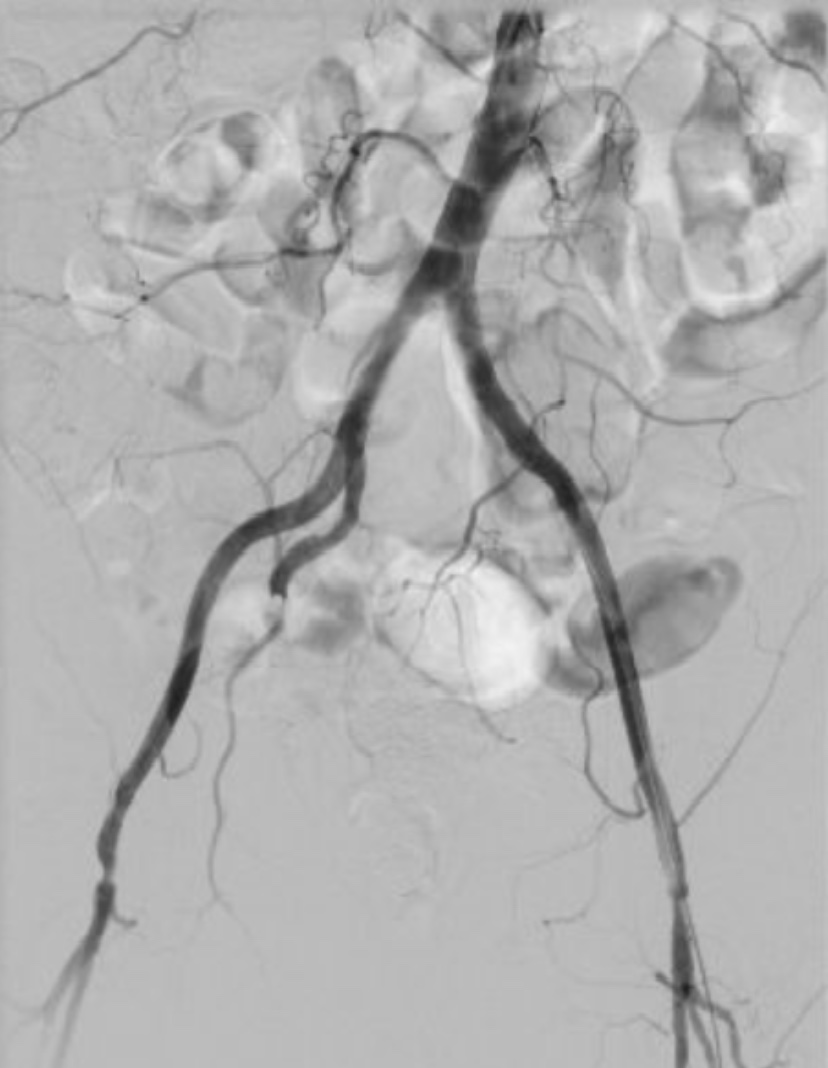

手术选择股动脉穿刺(介入微创)与双侧腹股沟下方做约6cm纵行切口(外科手术)联合的方式。术中造影显示腹主动脉远端、双侧髂总动脉不显影,说明该部位闭塞,无血流通过。医护人员经过紧张的3小时的手术,分别自患者双侧股动脉取出大量新鲜血栓,近端喷血良好。造影见腹主动脉、双侧髂动脉、股总动脉通畅,远端无充盈缺损。手术在凌晨1点顺利完成。

术后造影腹主动脉、双侧髂动脉、股总动脉通畅